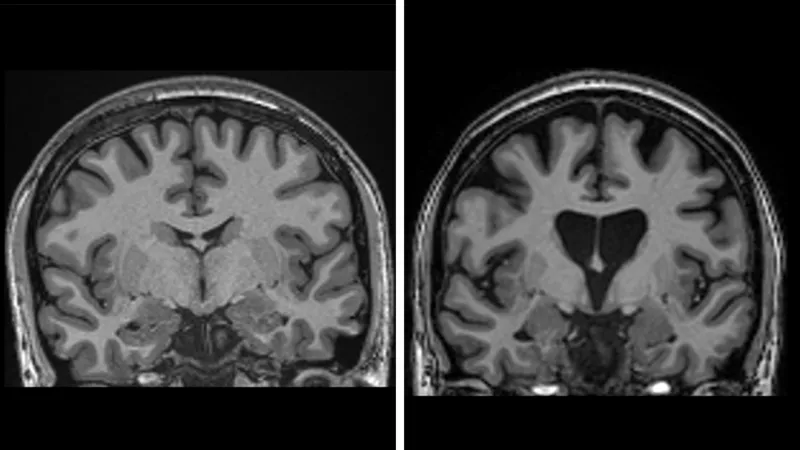

This is infused deep into the brain using real-time MRI scanning to guide a microcatheter to two brain regions – the caudate nucleus and the putamen. This takes 12 to 18 hours of neurosurgery.

The data showed that three years after surgery there was an average 75% slowing of the disease based on a measure which combines cognition, motor function and the ability to manage in daily life.

The data also shows the treatment is saving brain cells. Levels of neurofilaments in spinal fluid – a clear sign of brain cells dying – should have increased by a third if the disease continued to progress, but was actually lower than at the start of the trial.